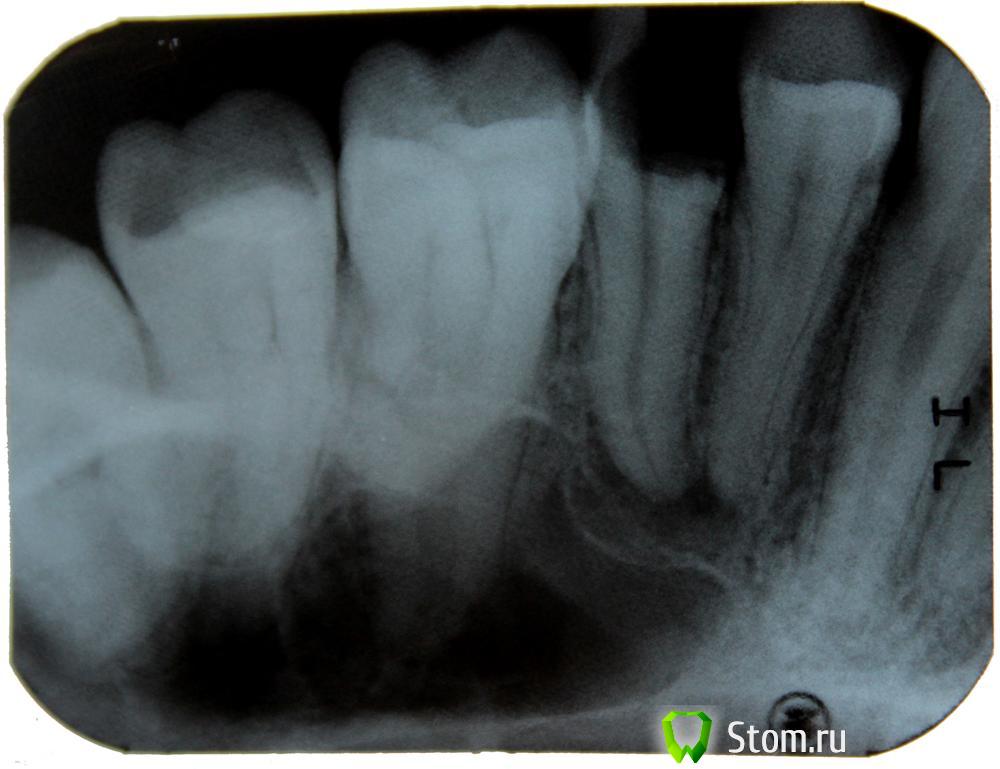

DsLog Опубликовано 31 января, 2012 Поделиться Опубликовано 31 января, 2012 Добрый день! Разрушены 2 зуба (5) верхней челюсти, врач клиники в которую обратился сказал что нужны снимки, принёс снимки, сказали что нужно удалять эти 2 зуба...удалять сказали в городской поликлиннике т.к. корень искревлён и они не смогут сами его удалить,.... после удаления предложили вариант: мост из металлокерамики со стачиванием двух соседних зубов и удалением из них нерва. Действую по принципу доверяй - но проверяй. Если зубы никак восстановить нельзя, то думаю что буду ставить импланты. Ссылка на комментарий

ger_berra Опубликовано 31 января, 2012 Поделиться Опубликовано 31 января, 2012 Удалять оба.На их место импланты.Не соглашайтесь на умышленное умертвление живых зубов!1-ый корень сгнил изнутри ниже уровня десны и вершины межальвеолярной перегородки.2-й высоты оставшихся твёрдых тканей недостаточно для изготовления ВКВ.Если только хирургическое удлинение.И то это будет компромисный вариант. Ссылка на комментарий

DmitrySH Опубликовано 31 января, 2012 Поделиться Опубликовано 31 января, 2012 По данным снимкам не брался бы судить удалять или нет. Если удалять, то На их место импланты.Не соглашайтесь на умышленное умертвление живых зубов!.А еще можно с ортодонтом проконсультироваться. Если оба зуба удаляются, то я бы предложил рассмотреть вариант ортодонтического закрытия свободного места. Ссылка на комментарий